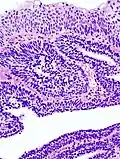

Micrograph of an inverted papilloma of the urinary bladder; H&E stained

An inverted papilloma, also known as Ringertz tumor,[1] is a type of tumor in which surface epithelial cells grow downward into the underlying supportive tissue. It may occur in the nose and/or sinuses or in the urinary tract (bladder, renal pelvis, ureter, urethra). When it occurs in the nose or sinuses, it may cause symptoms similar to those caused by sinusitis, such as nasal congestion. When it occurs in the urinary tract, it may cause blood in the urine.